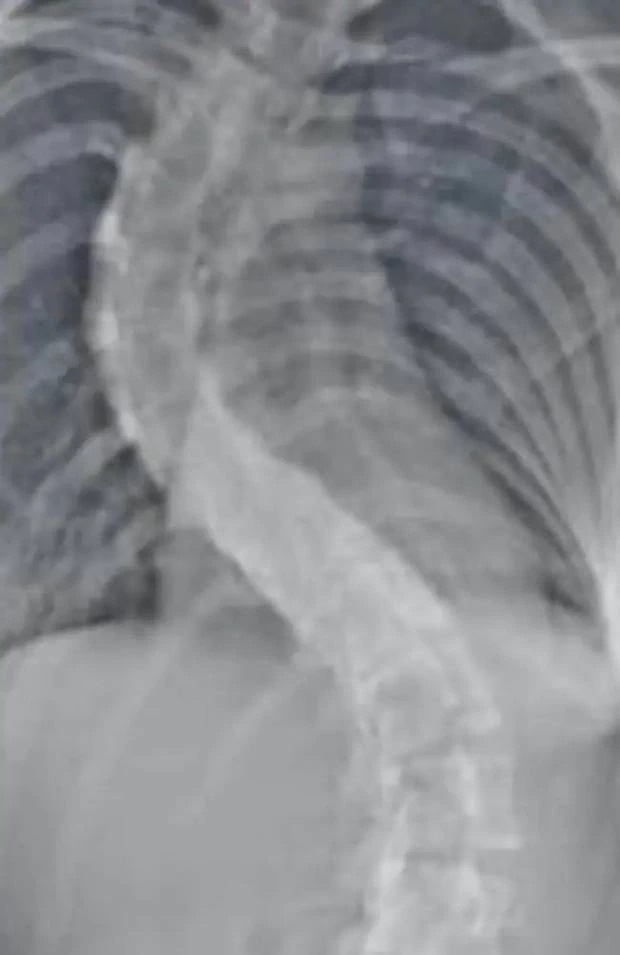

Hình ảnh chụp X-quang cột sống của Vanessa hồi 12 tuổi. Ảnh: NZ Herald.

Hình chụp X-quang cho thấy cô gái nhỏ mắc căn bệnh cong vẹo cột sống nặng, như hình chữ S.